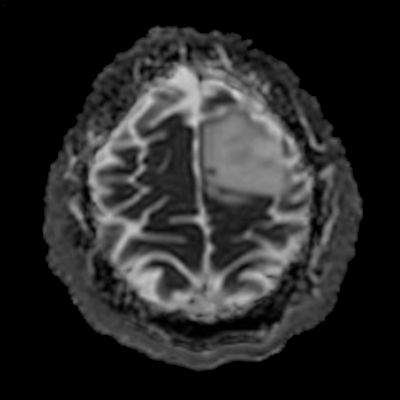

- ADC görüntülerde lezyonda sinyal artışları ile karakterize difüzyon artışı (ok) izleniyor. Bu alana yönelik yapılan multivoksel MR spektroskopi incelemesinde (ok) kolin pikinde artış ve NAA pikinde azalma izleniyor. Cho/Cr oranı 1.76 ölçülüyor.

- DAG’de düşük ADC değerleri varsa bu daha yüksek mitotik aktiviteyi gösterebilir (grade 3–4).